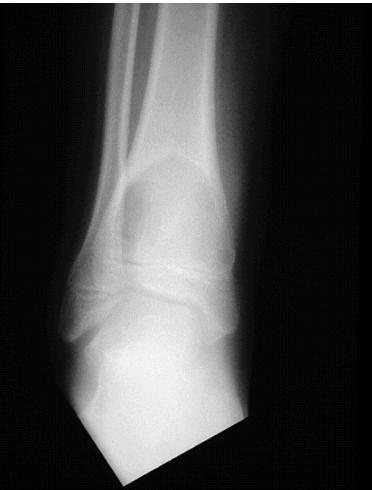

Aneurysmal Bone Cyst

site: Distal tibial

size: Involving most of distal part

matrix: Cortical expansion, radiolucent matrix, well defined, narrow zone of transition

soft tissue involvement: no peristeal reaction